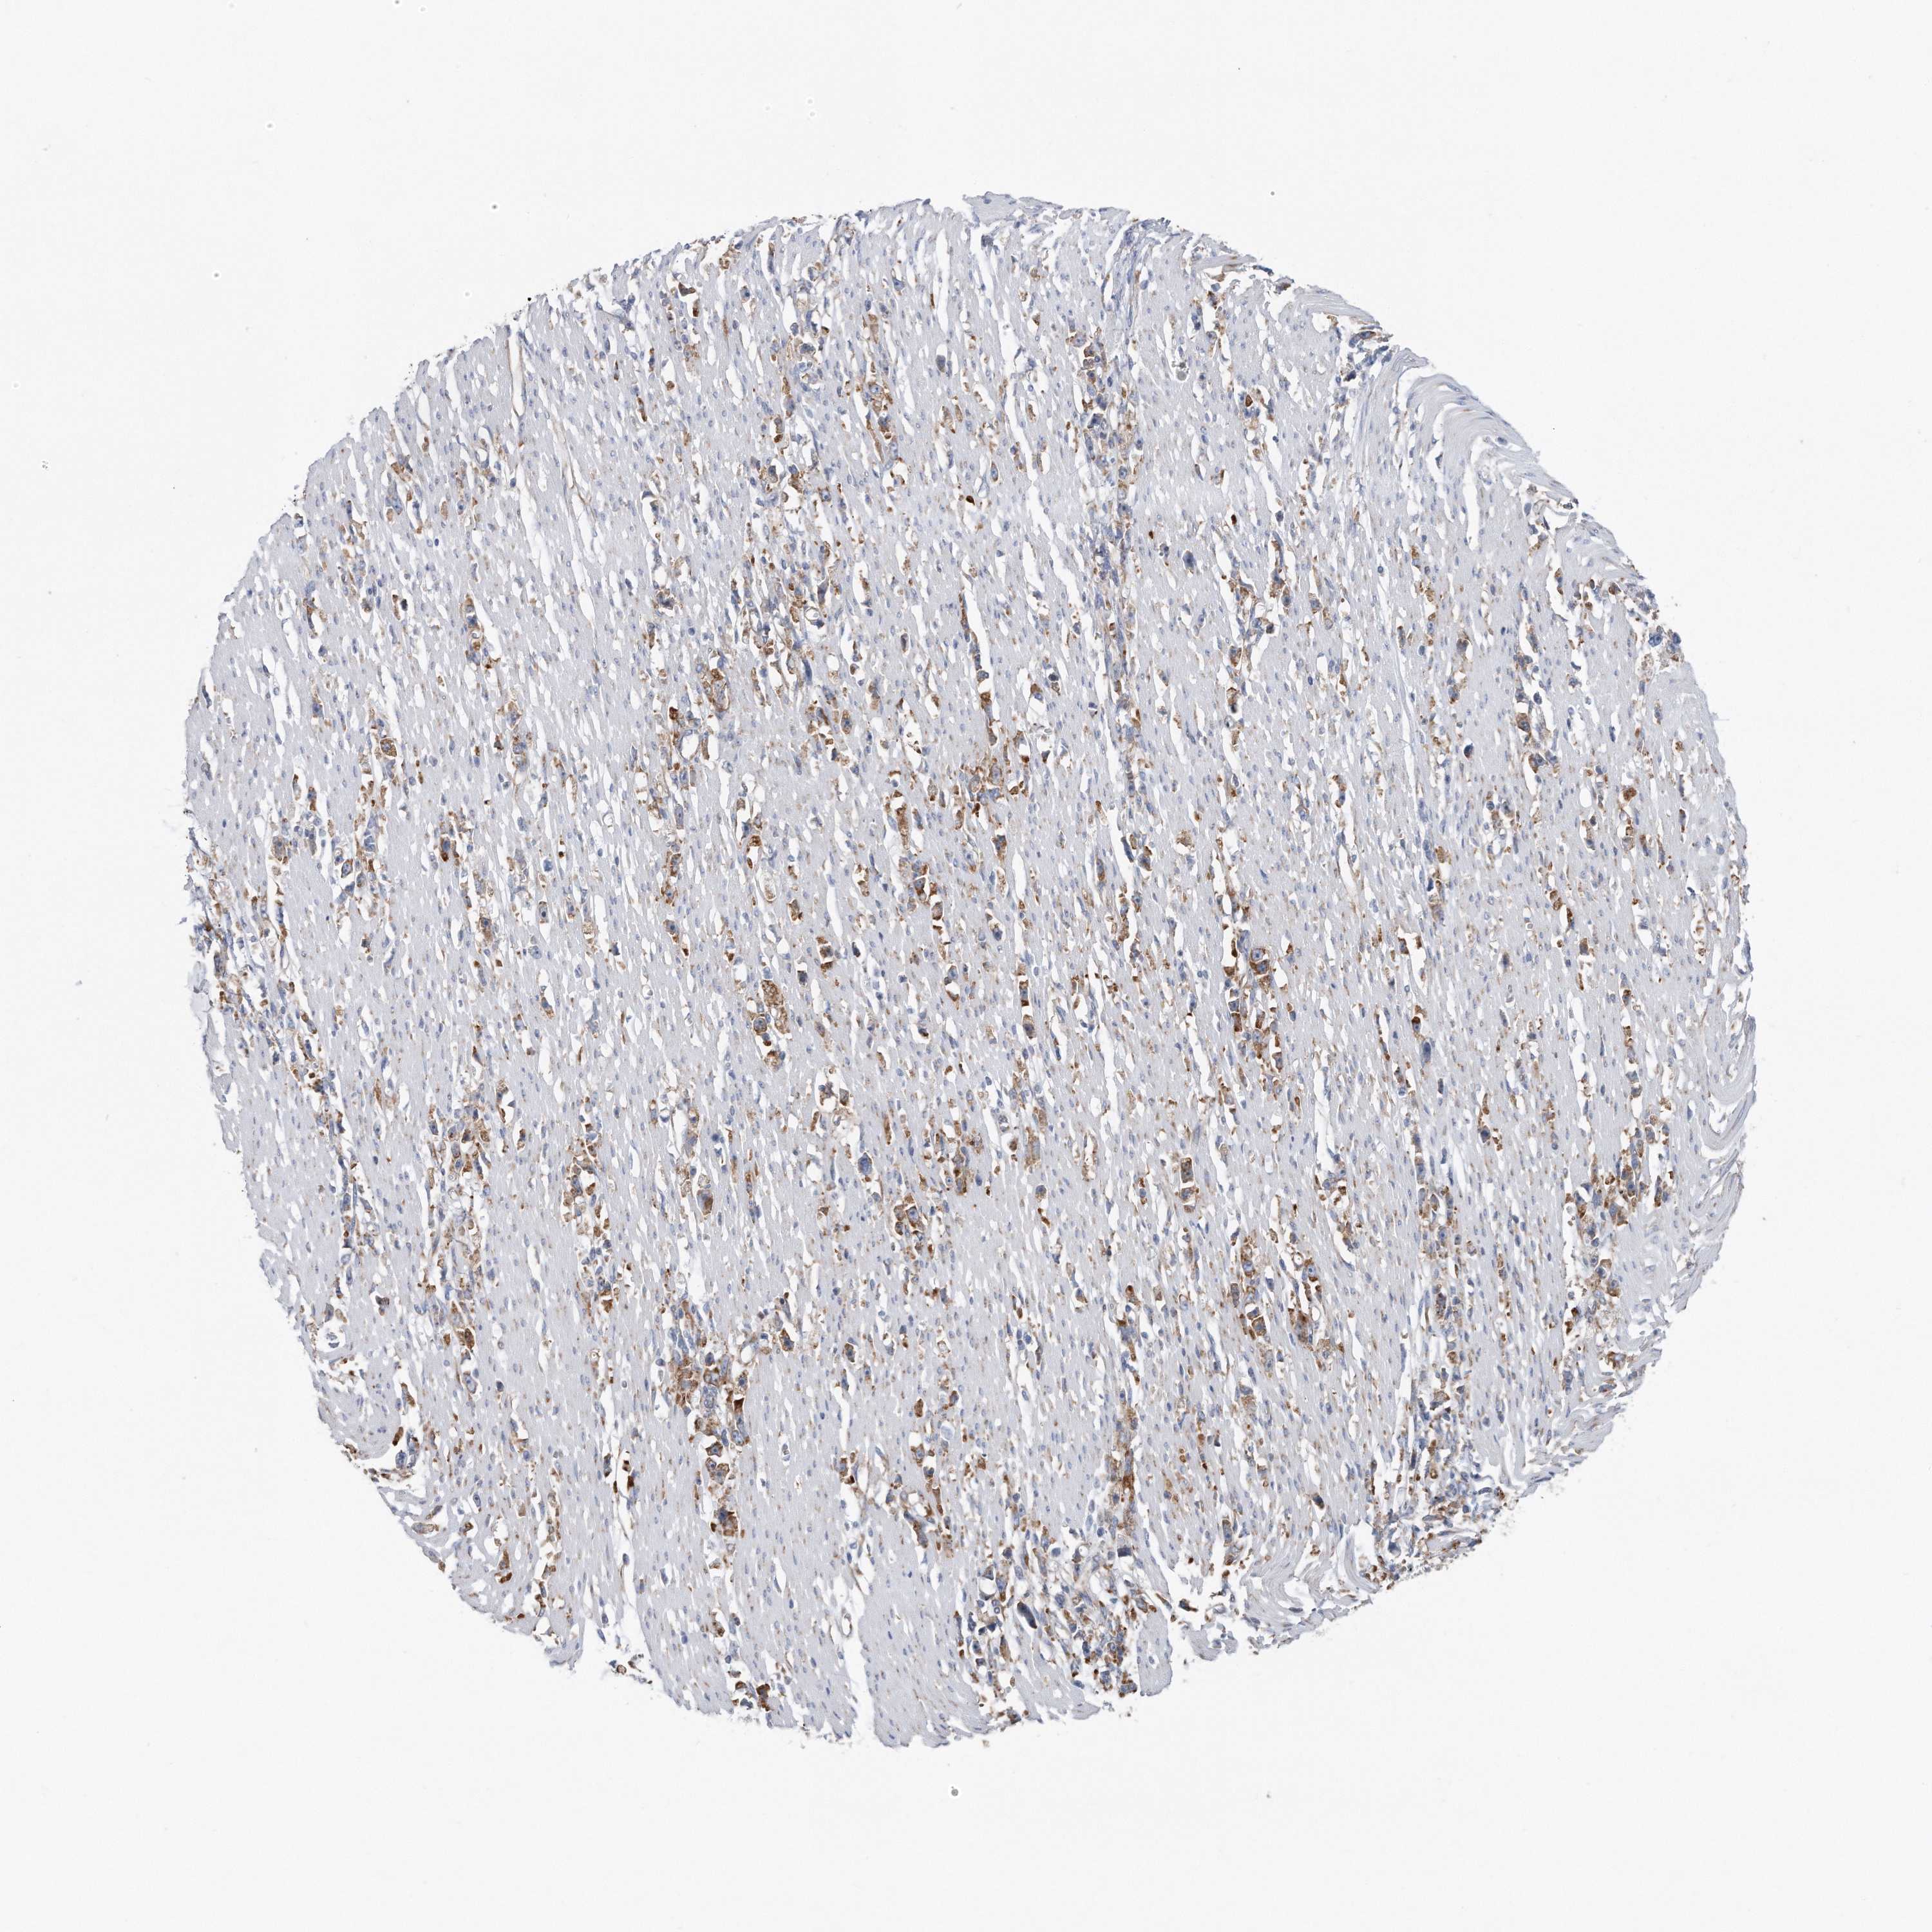

STOMACH CANCER - Protein expressioni

A mouse-over function shows sample information and annotation data. Click on an image to view it in a full screen mode. Samples can be filtered based on level of antibody staining by selecting one or several of the following categories: high, medium, low and not detected. The assay and annotation is described here.

Note that samples used for immunohistochemistry by the Human Protein Atlas do not correspond to samples in the TCGA dataset.

Antibody stainingi

Antibody staining in the annotated cell types in the current human tissue is reported as not detected, low, medium, or high, based on conventional immunohistochemistry profiling in selected tissues. This score is based on the combination of the staining intensity and fraction of stained cells.

Each image is clickable and will lead to virtual microscopy that enables deeper exploration of all samples and also displays staining intensity scores, fraction scores and subcellular localization as well as patient and tissue information for each sample.

Antibody CAB037301

Staining

High

Medium

Low

Not detected

Intensity

Strong

Moderate

Weak

Negative

Quantity

>75%

75%-25%

<25%

None

Location

Nuclear

Cytoplasmic/membranous

Cytoplasmic/membranous,nuclear

Adenocarcinoma, NOS